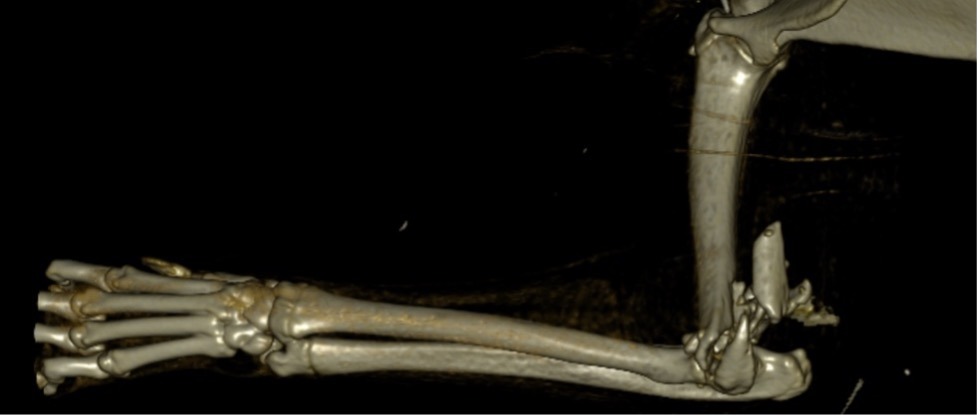

Exemple 3 :

Figure 9 : Pré-Op

Figure 10 : Opération